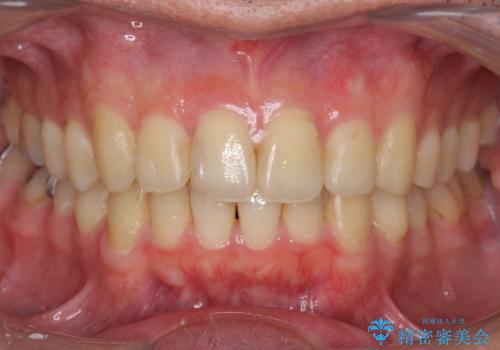

[ 前歯のねじれ・がたつき ] マウスピース矯正

![[ 前歯のねじれ・がたつき ] マウスピース矯正の症例 治療前](https://seimitsushinbi.jp/wp/wp-content/uploads/2024/02/4007c6479f6bce11863dcdd32ed5e39b-500x350.jpg?v=1708502552)

![[ 前歯のねじれ・がたつき ] マウスピース矯正の症例 治療後](https://seimitsushinbi.jp/wp/wp-content/uploads/2024/02/e7a01485e4f4dd0da04705fde4cc34cc-500x350.jpg?v=1708502585)